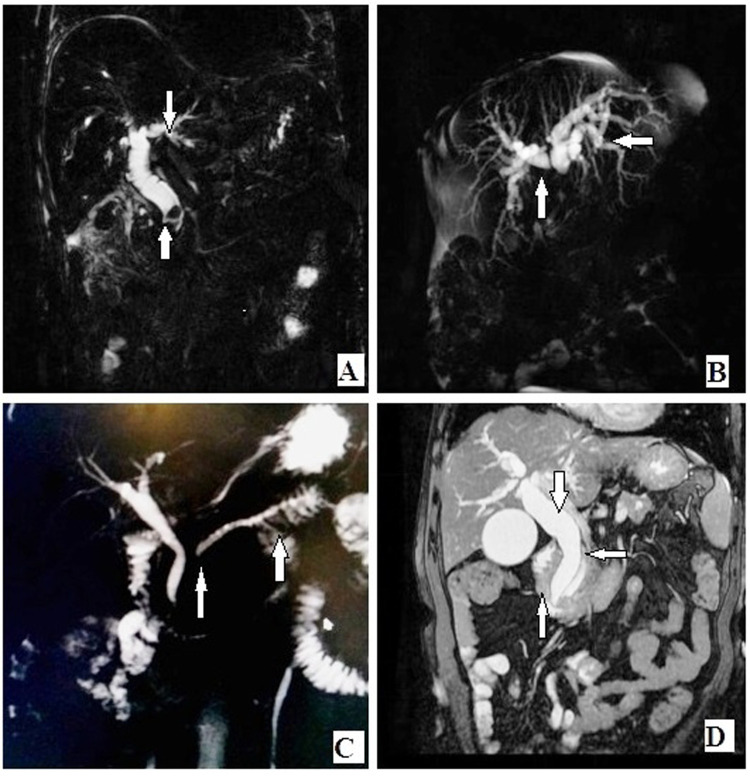

CBD stricture

ERCP-proven CBD strictures were correctly diagnosed by MRCP in 10 out of 12 ERCP-proven cases, and MRCP correctly excluded stricture in 47 cases. The true-positive, true-negative, false-positive, and false-negative results were 10, 47, 1, and 2, respectively. The sensitivity and specificity were high at 83.33% (95% CI: 51.59–97.91) and 97.92% (95% CI: 88.93–99.95), respectively, with reference to ERCP. The PPV, NPV and accuracy were 90.91%, 95.92%, and 95.9%, respectively (Figure 1A,B).

Choledocholithiasis was found in 63% of cases of MRCP and 70% of cases of ERCP. MRCP and ERCP detected CBD strictures in 18% and 20% of cases, respectively. Both techniques detected pancreatic duct dilatation in 18% of cases each and pancreatic duct stricture in 15% and 16% of cases, respectively. Periampullary carcinoma was diagnosed in 15% and 16% of MRCP cases, respectively. There was no significant difference between MRCP and ERCP in the evaluation of these pathologies (Figures 1 and 2).